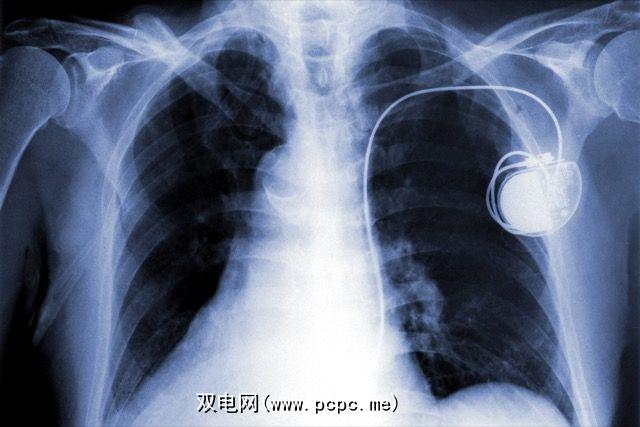

您的健康待命

这可能是所有人中最恐怖的前景。 Forrester最近的一份报告预测,明年我们将开始看到健康设备受到勒索软件的攻击。起搏器,糖尿病植入物,健康监测器,深脑刺激器,甚至紧急警报系统,都可能被要求缴纳释放费的黑客俘虏。当然,您可能会争论说,老年人并不是实现此目标的最佳选择,因为他们可能不知道比特币是什么,但是威胁仍然存在。

植入计算机的设备可以正常工作,可能会为连接的可植入视网膜或其他光学技术铺平道路。

我们拥有的这些设备越多,我们就越容易受到潜在的攻击。到目前为止,医疗行业在可穿戴设备的网络安全方面还没有做得很好。如果我们不想让人质被人质绑架,他们就必须加强。